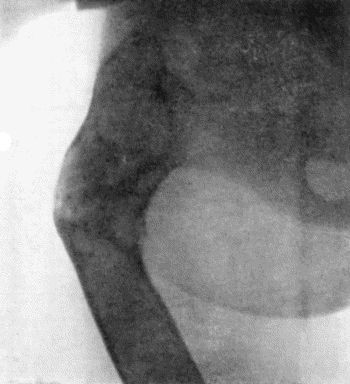

490 145.Radiogram of Myeloma of Humerus

492 146.Periosteal Sarcoma of Femur